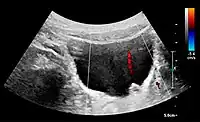

Under normal conditions, the ureter is not seen with US. However, in, e.g., urinary obstruction and vesicoureteric reflux with dilation of the ureter, the proximal part in continuation with the renal pelvis, as well as the distal part near the ostium can be evaluated (Figure 14).[1]